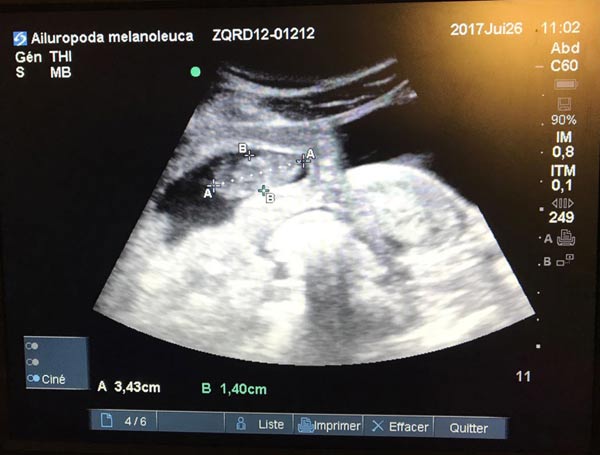

Chinese panda Huan Huan, which is on loan to France, is expecting twin cubs, according to the zoo which carried out a medical examination and revealed the results exclusively to China Daily on Tuesday. [Photo provided to China Daily] |